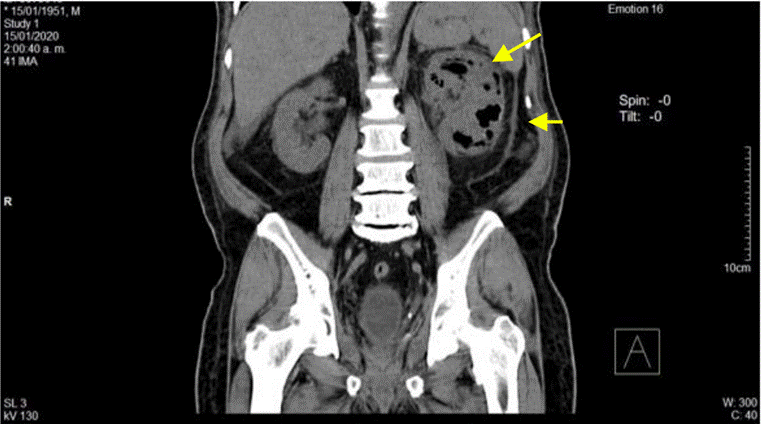

La ecografía abdominal total mostró hallazgos sugestivos de PNE izquierda (Figura 1), por lo que se solicitó valoración por urología; este servicio indicó continuar con la misma terapia antibiótica y realizar UROTAC que mostró microlitiasis renal bilateral, litiasis ureteral izquierda y proceso infeccioso inflamatorio con presencia de gas en el riñón izquierdo, lo que indicó diagnóstico de PNE izquierda tipo 2 (Figuras 2 y 3). Ante los hallazgos radiológicos y el reporte de urocultivo positivo para Escherichia coli multisensible, se decidió hacer rotación de cubrimiento antibiótico a carbapenémicos debido al alto riesgo de mortalidad.

La paciente fue valorada por el servicio de medicina interna, el cual consideró hospitalizar con diagnóstico de infección de vías urinarias complicada sin respuesta a tratamiento antibiótico inicial, enfermedad diarreica aguda y enfermedad renal crónica agudizada, por lo que se inició manejo con fluidoterapia, cobertura antibiótica con piperacilina tazobactam, ajustado a función renal (TFG 20,2 mL/min/1,73 m2), y se solicitaron cultivos. Asimismo, se realizó ecografía con evidencia de riñón izquierdo aumentado de volumen, de contornos regulares, con presencia de ecogenicidades puntiformes en el grupo calicial superior con aspecto de gas. Se solicitó UROTAC (Figuras 5 y 6) que reportó gas en el sistema colector del riñón izquierdo, más específicamente en pelvis renal izquierda y dentro del uréter izquierdo, además de anomalía congénita de fusión renal (riñón en herradura), hidronefrosis leve izquierda con pelvis globulosa y múltiples litiasis a nivel de uréter distal y unión ureterovesical izquierda. La paciente tuvo expulsión espontánea de litos y descenso de azoados hasta niveles basales (1,9 mg/dL).

Dados los hallazgos compatibles con PNE Huang I (pielitis enfisematosa y ureteritis enfisematosa izquierda), se solicitó valoración por servicio de urología.